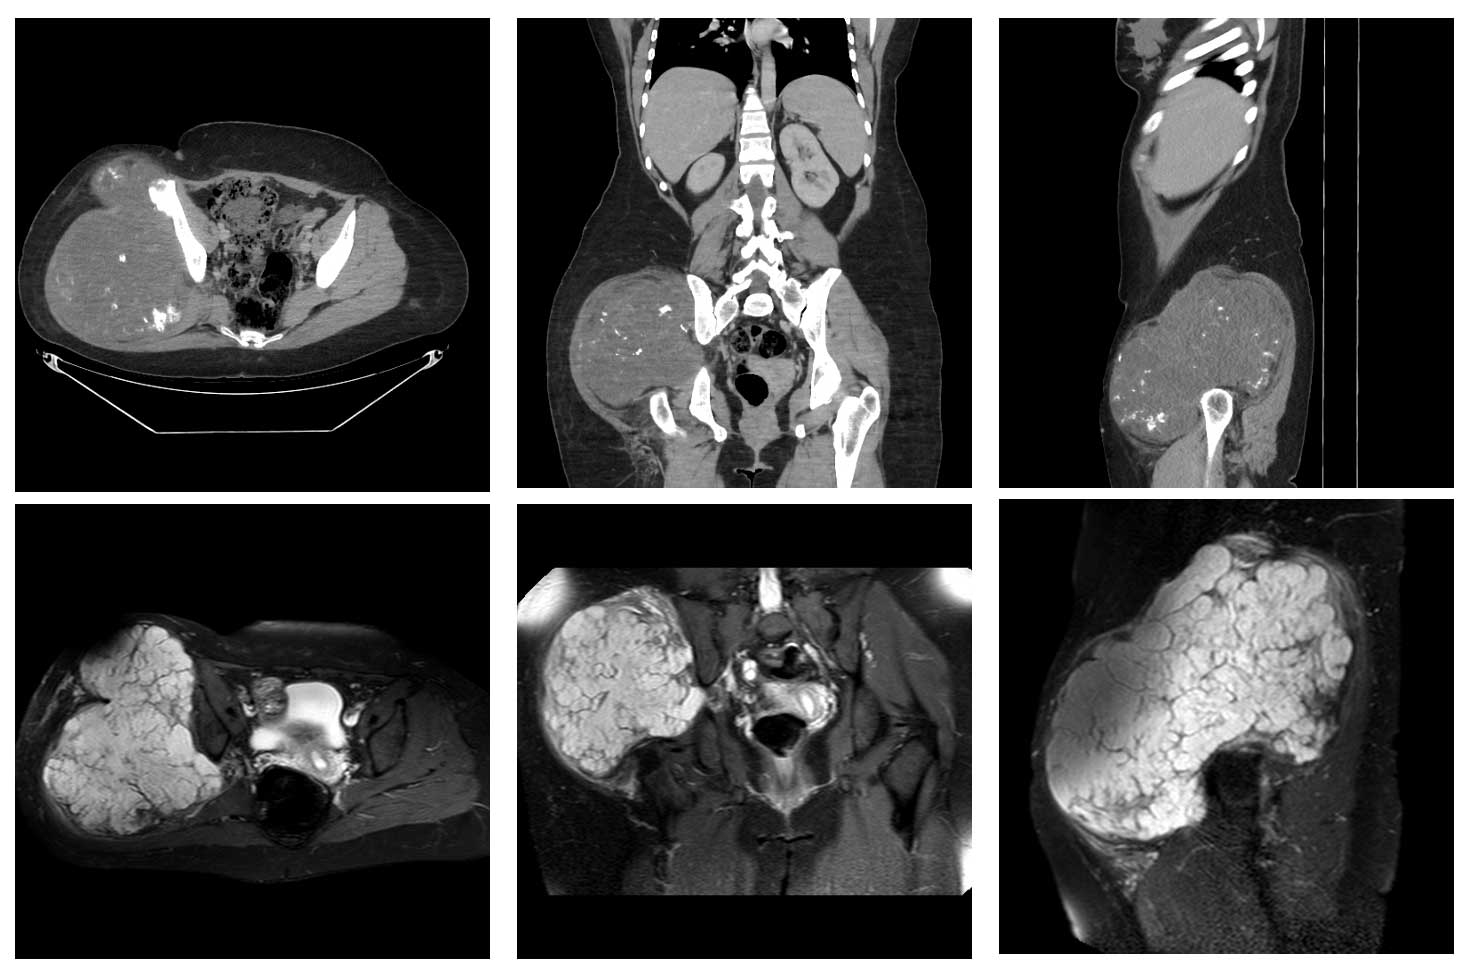

Ameliyat Öncesi: Tomografide MR’da büyük tümör dokusu görülmekte.